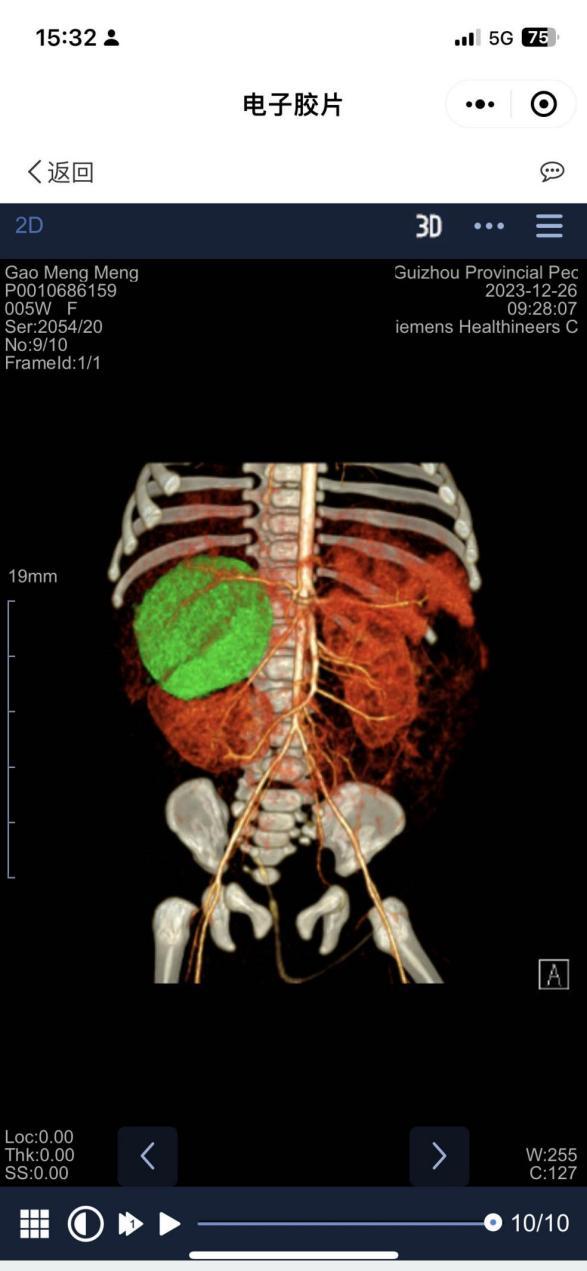

CT三维重建图像(绿色为肿瘤组织)

近日,患儿在全麻下行腹膜后肿瘤切除术,术中可见肿瘤来源于右侧肾上腺,大小55x55x4mm。肿瘤不仅占据了很大的空间,且与右侧肾脏,肝门静脉,肝动脉,腔静脉粘连紧密,若稍有不慎,即可能出现血管破裂大出血的情况。泌尿外科安妮妮主任与普外科唐应明主任术中密切配合,小心分离结扎肿瘤血管,最终将肿瘤完整切除。术后,患儿在小儿外科全体医护人员的精心照顾下,病情逐渐好转,现已康复出院。